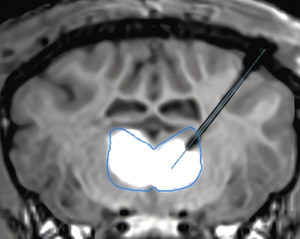

Figure 2: Magnetic resonance imaging (MRI) showing a real-time infusion into the thalamus using the Neurochase Acute Drug Delivery System of a gene therapy co-labelled with MRI contrast agent gadolinium to enhance visibility.

To overcome this, the final design of the Neurochase Acute Drug Delivery System focuses on distributing the infusate along the exposed length of the cannula to maintain lower pressure at any single point, minimising tissue damage and maximising distribution (Figure 2). The result is a system designed to control reflux, while achieving more than 70% coverage of the target structure.